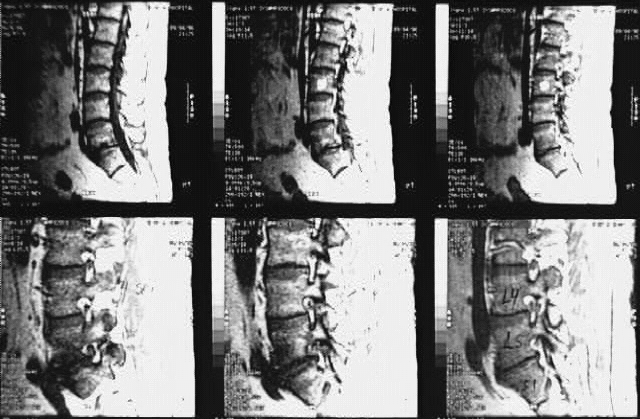

Radiology Images

Back- Lumbar Spine MRI Sagittal 4